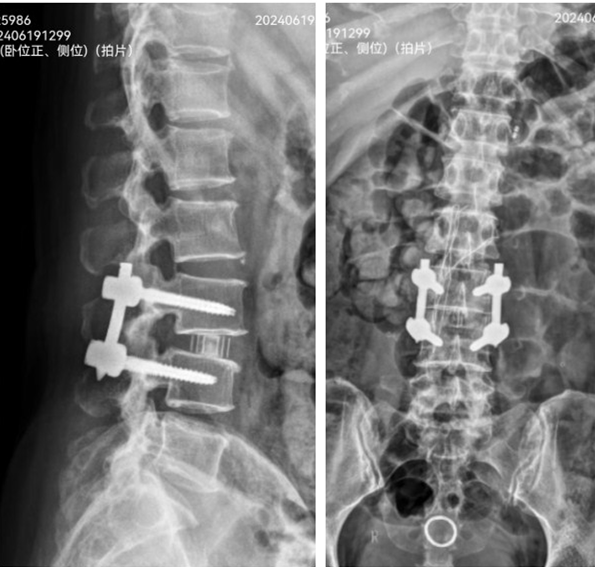

医生经患者侧腹部的3.5厘米切口完成腰椎融合手术。

术后检查显示,L3/4恢复正常椎间高度和生理序列。